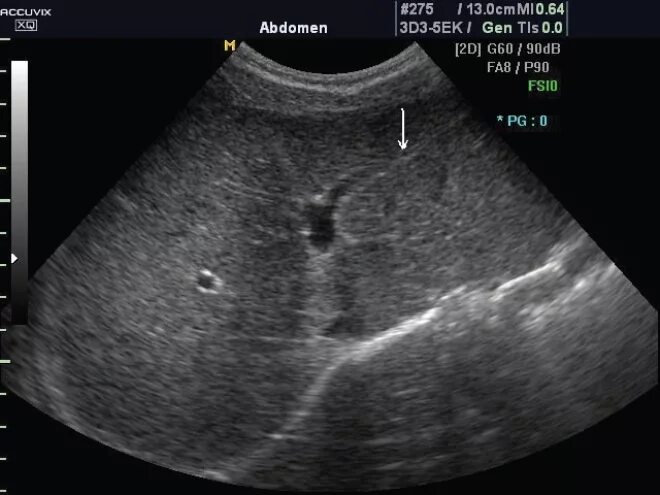

Белое пятно на узи